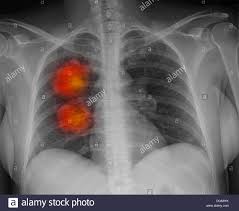

- Exploración con PET: Esta prueba es la más eficaz para comprobar si existe metástasis. El médico inyectará en la vena del paciente una cantidad pequeña de glucosa radiactiva y, a continuación, el escáner rotará alrededor del cuerpo para tomar imágenes de los lugares que usan esa glucosa. Los tumores malignos son más visibles (brillan en las imágenes) porque al estar más activos consumen más glucosa que las células normales.